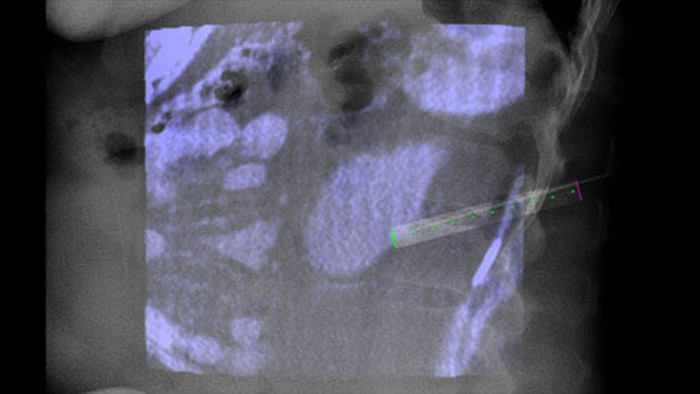

XperGuide bietet eine besonders präzise Live-Bildführung für jede Nadel zur Zielposition. Hierfür wird das Durchleuchtungsbild mit den vorab geplanten Bewegungsverläufen überlagert.3